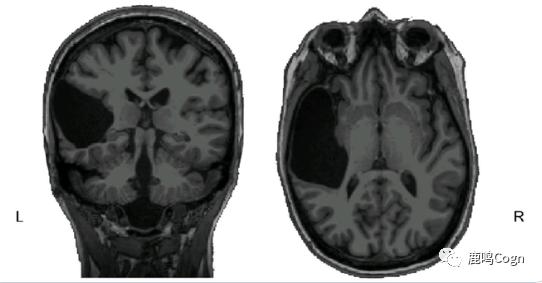

前天(5月28日),MIT的神经科学家Ev Fedorenko在BioRxiv上登了一篇非常有意思的个案研究。2016年,一名先天没有左侧颞叶(left temporal lobe,言语功能相关的重要脑区,如下图)的女士EG(化名)参与了她的研究。EG女士从小一直正常生活,直到25岁才得知自己先天缺少颞叶,也就是说颞叶的缺失对她而言并没有影响到生活。

EG女士的大脑:先天左侧颞叶缺失

和大多数先天脑损伤的患者一样,EG的言语功能和其他认知功能并没有受损。也就是说,由于大脑的可塑性,EG原本左侧颞叶的功能在其他脑区中得到了代偿。具体而言,普通人的言语优势半球(dominant  hemisphere, DH)是左半球(LH),而EG的言语优势半球是右半球(RH),她的右半球有着完好的语言网络